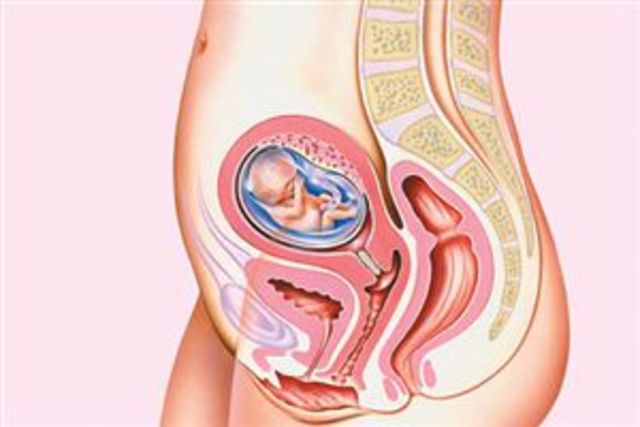

Third Trimester

• Month 8

Month 8

Fat is formed. The positioning of the fetus can change, even in the overcrowded uterus. More activity is common within organs. Digestive organs produce more waste.